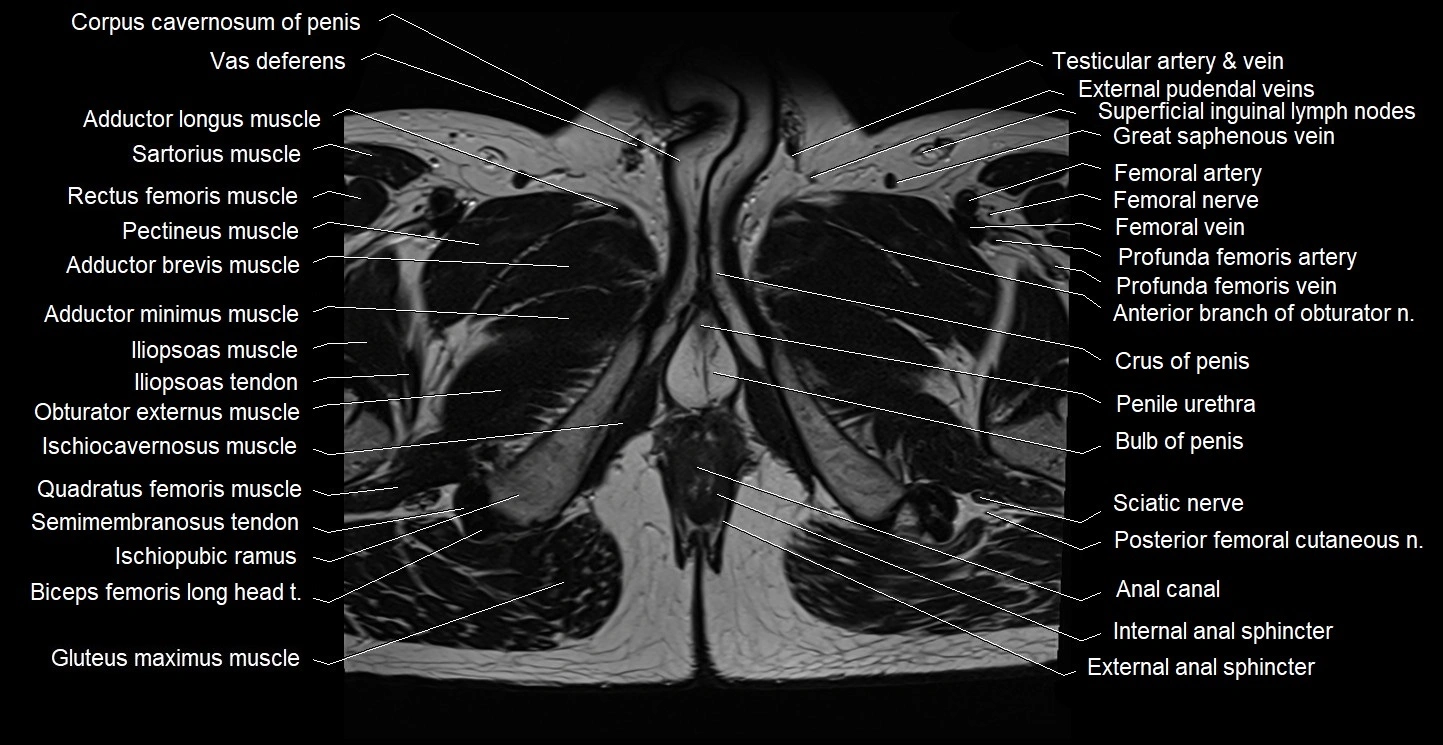

- Bulb of Penis

- Corpus cavernosum

- Crus of penis

- External anal sphincter

- Internal anal sphincter

- Ischiocavernosus muscle (Male)

- Ischiopubic ramus

- Penile urethra

- Posterior femoral cutaneous nerve

- Sciatic nerve